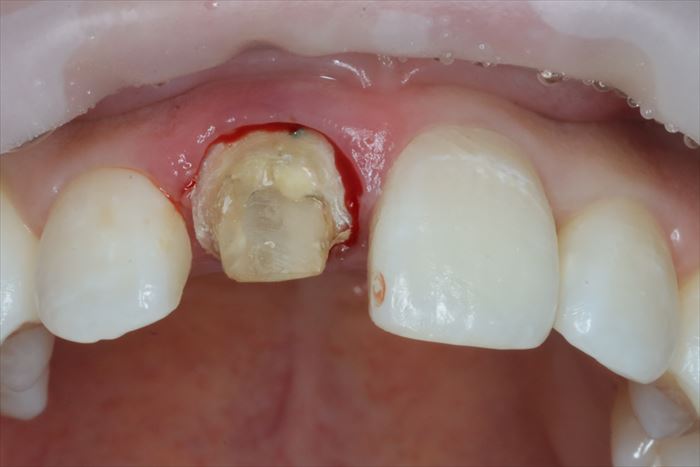

まずは現状の仮歯が外れました。

続いて支台築造と周囲の歯質が取れました。

まだ歯根が残っていますが歯肉が入り込んでいたことが判ります。

残っていた歯根を抜歯し、顕微鏡下で抜歯窩内部の掻爬を終えました。

心配していた唇側の骨は無事に保存できました。

このように満身創痍な状態で今日までよく頑張ってくれました。